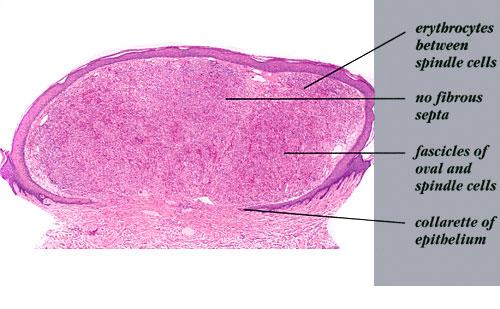

Nodular lesions consist predominantly of spindle cells arranged in bundles and interlacing fascicles and interspersed, irregular, slit-like vascular spaces without endothelial linings. Advanced lesions may display pronounced pleomorphism, nuclear atypia, and mitotic figures. At the periphery of solid tumors, (lymph) angiomatous-like portions of KS with bizarre vascular lumina and intravascular and extravasated erythrocytes, as well as siderophages, may be preserved. Erythrocytes, which appear as eosinophilic globules, are trapped within the slits and clefts formed by the spindle cells and erythrophagocytosis are occasionally observed. As in all other stages of KS, a moderate inflammatory infiltrate consisting of lymphocytes, histiocytes, plasma cells, and, sporadically, neutrophils is regularly present.